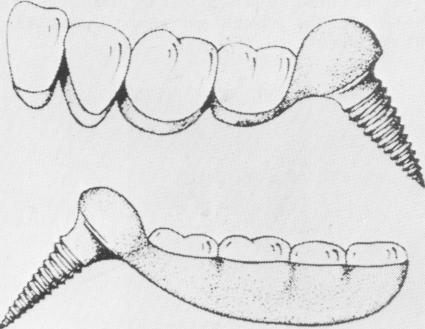

An early implant designed by Dag is an interesting attempt to use what is basically an orthopedic type screw as a dental implant (Fig. 5-11) . Although such a screw might be successful embedded in a bone

Fig. 5-11. Dag's implant was a variation of an orthopedic screw. As a dental implant, Dag's design has several flaws. Its impact area is too large, there is no provision for drain-age, and the threads are much too close together. (Courtesy Dag.)